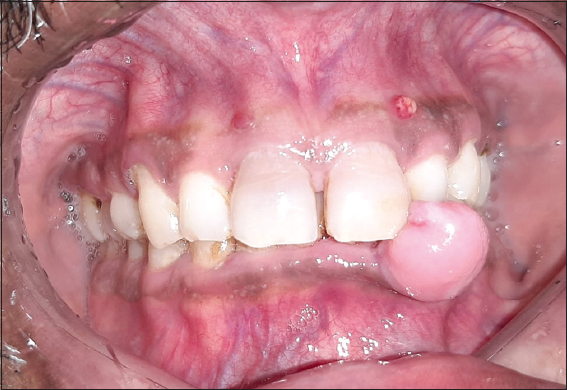

A 49-year-old man with a 4-year history was presented to the outpatient periodontics department for evaluation of a painless, slowly growing, firm gingival mass in the left lower front tooth region [Figure 1]. Its enlargement began as a small nodule and progressed till it impinged on mastication. He had no relevant medical history and was not on any medication. Intraoral examination revealed a single sessile swelling of approximately 10 mm × 7 mm that extended mesiodistally from teeth #32 to #33 and attached intraorally in the left lower gingiva [Figure 2].

Figure 1: Preoperative view

Figure 2: Extension of the swelling